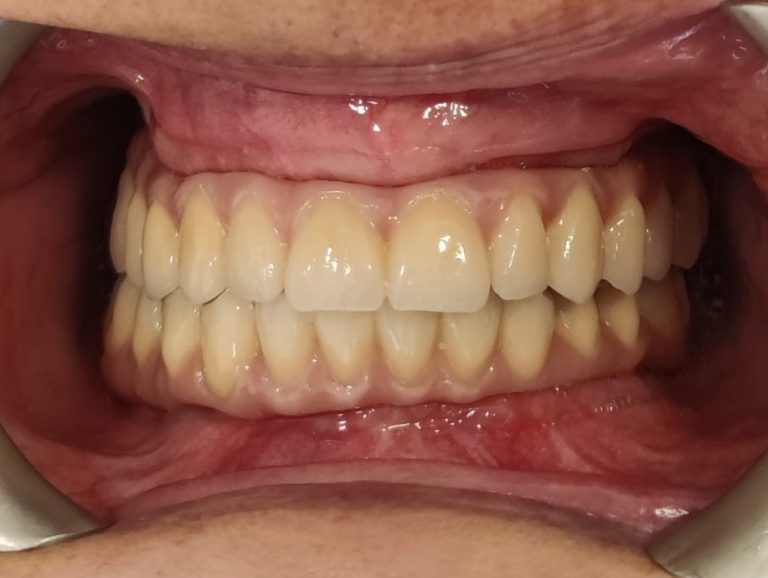

Páciensünk esetében a 3 hónapos kontrollvizsgálaton a felvételek és vizsgálatok azt mutatták, hogy az implantátumok sikeresen integrálódtak a csontba, komplikáció nem merült fel. Ez idő alatt a páciens az ideiglenes fogsorral teljes életet élt: visszanyerte rágóképességét, és megszokta új mosolyát, amely működésében szinte megegyezett a természetes fogakkal.

A 3 hónap leteltével megkezdtük a fogpótlás véglegesítését. Lenyomatot vettünk figyelembe véve a páciens egyéni igényeit, mosoly-esztétikai szempontjait (fogak formája, színe, arc karaktere). Ezzel elkezdődött a végleges körhíd elkészítése, amely prémium minőségű anyagokból (cirkónium-kerámia) készült a tartósság és esztétikum érdekében.

A végleges All-on-4 híd gyönyörűen illeszkedik az ínyhez, formája és színe teljesen természetes hatású. A kerámiahíd könnyen tisztítható és rendkívül strapabíró, így megfelelő szájhigiénia mellett akár élethosszig is megőrizheti funkcióját és esztétikumát.

Végleges kerámia all-on-4 fix fogpótlás 3 hónapos kontroll után